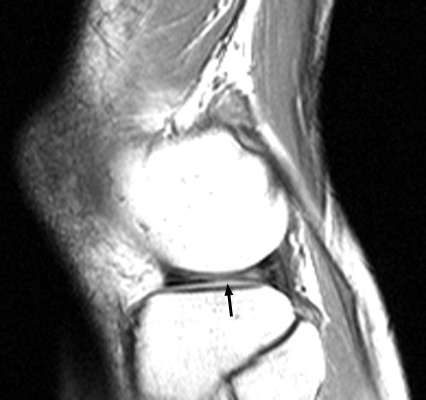

Multiple sagittal T1 weighted images which reveal loss of the normal bow-tie appearance of the meniscus. The "absent bow tie sign" is another good sign of a bucket handle tear of the meniscus. The absence of the normal bow-tie is secondary to the displaced fragment which makes up the "handle" of the bucket. Requirement for the absent bow tie sign mandates that the normal requirement of at least two adjacent sagittal images with a normal meniscal body segment appearance is not present.

- Click on the image for a larger versionA - Click on the image for a larger versionB - Click on the image for a larger versionC